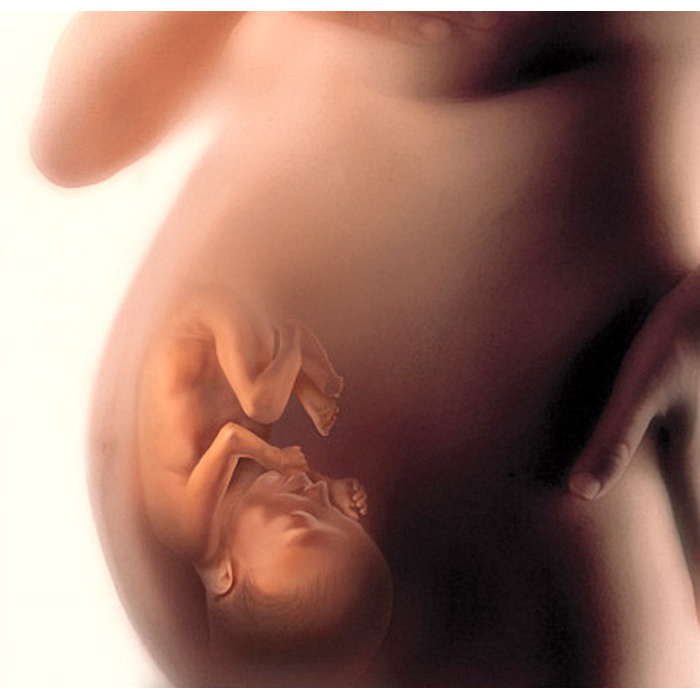

Этапы развития ребенка в утробе: фотографии и ультразвуковые снимки

Раздел: Лаборатория идей